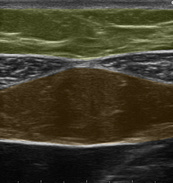

みぞおちに当てて出てくる画像のパターンによって、その人の「これまでの生活習慣」と「今後改善しなければならないこと」が分かります。

【理想的パターン】

【過剰な食べ過ぎと筋トレ不足パターン】

【隠れ肥満(食べ過ぎ)パターン】

【砂糖の過剰摂取と有酸素運動不足パターン】